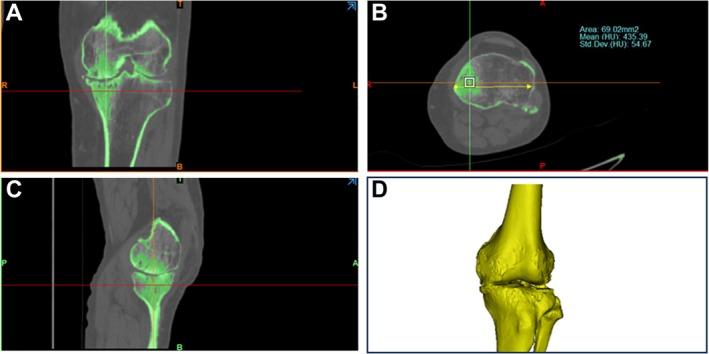

METHODS

Our retrospective cohort study enrolled a total of 97 patients from December 2018 to December 2019, categorized into drilled and nondrilled groups, with their computed tomography (CT) knee joint images documented. The proximal tibia image was divided into nine regions, the BMD of each region calculated, and CT values compared between the affected and normal sides. We established finite element models to analyze the drilling and stress distribution. The differences in CT values were assessed using the paired t test and Wilcoxon signed-rank test.

方法

我们的回顾性队列研究共纳入了2018年12月至2019年12月期间的97例患者,分为钻孔组和未钻孔组,并记录了他们的膝关节计算机断层扫描(CT)图像。将胫骨近端图像分为九个区域,计算每个区域的骨密度,并比较患侧和正常侧的CT值。我们建立了有限元模型来分析钻孔和应力分布。使用配对t检验和Wilcoxon符号秩检验评估CT值的差异。